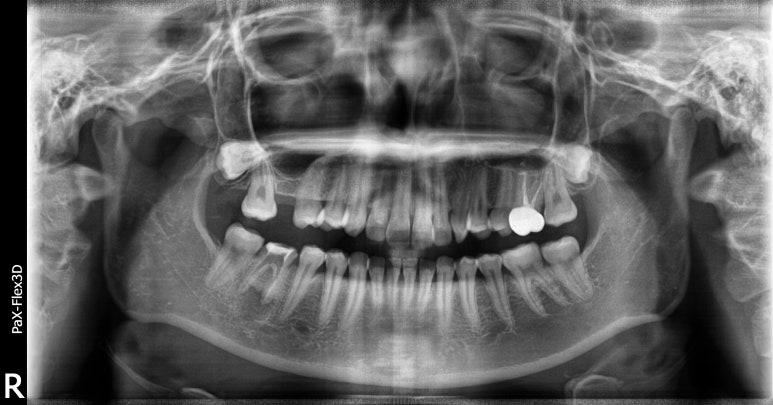

임플란트 수술 전

20대 남성

2023-07-21

가장 최근에 내원하신 20대 초반의 남성분인데요.

내원 2주 전부터 오른쪽 아래 치아에 통증이 있어서 임플란트 상담을 위해 찾아오셨습니다.

엑스레이 보시면 오른쪽 아래(사진상 왼쪽) 사랑니와 #47 치아가 맞닿아있는 부분이 까맣게 보이시죠?

어금니 맨 뒤는 칫솔이 잘 닿지 않는데다가 매복사랑니까지 맹출하면서 #47 치아를 밀어내고,

결국 치아가 썩어 발치 후 임플란트를 하셔야 하는 케이스였습니다.